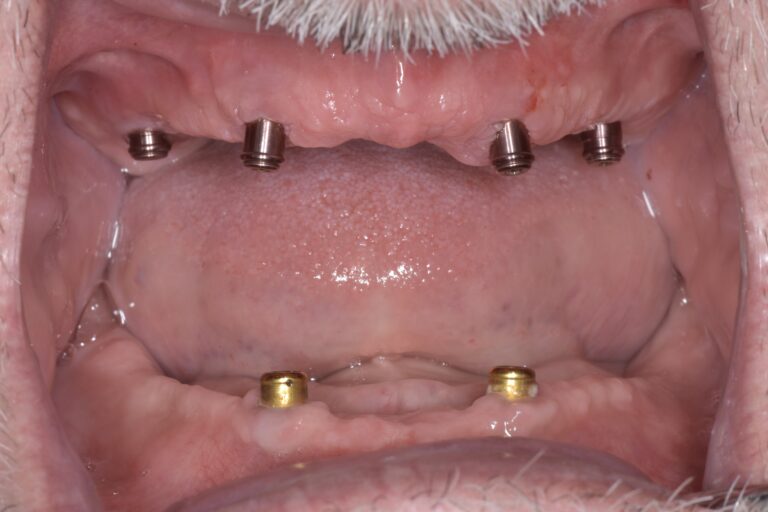

オールオン4(All-on-4)とは、上下それぞれ最小4本のインプラントを埋入し、固定式の歯を装着する治療法です。

短期間で噛み合わせと見た目の回復が期待でき、以下のような方に適しています。

• 多くの歯を失ってしまった方

• 総入れ歯が合わず、よく噛めない方

• 入れ歯が外れることに不安がある方

オールオン4は治療計画・手術・補綴まで高度な技術が必要な治療です。

当院では、経験豊富なインプラント専門医が、患者さまと十分に相談を行い、万全の体制で治療に取り組みます。

仙台市でオールオン4をご検討中の方は、まずはご相談ください。

インプラント治療 オールオン4

治療後

虫歯と歯周病でボロボロになった歯の抜歯を行い、当日に4本のインプラントを埋入し,仮歯まで装着しました。